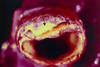

Aneurisma vascular

Dilatação > 50% do diâmetro original do vaso.

Pseudoaneurisma

Hematoma pulsátil que não está contido por todas as camadas da parede vascular.

O aneurisma verdadeiro é aquele que contém todas as camadas da parede arterial.

Morfologia mais comum dos aneurismas?

Fusiforme.

Morfologia de aneurismas com maior risco de ruptura?

Sacular.